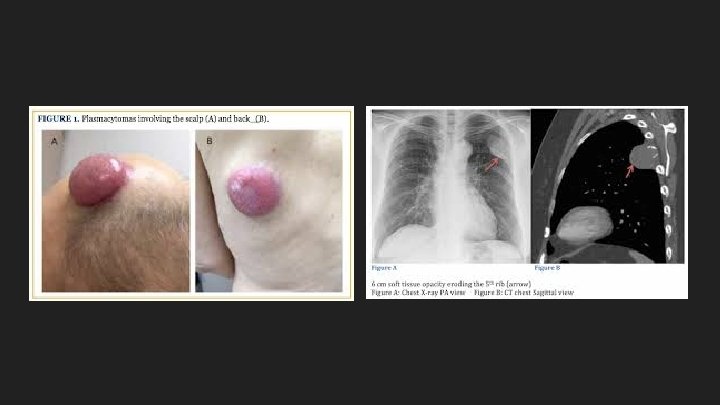

Multiple Myeloma ● When there are multiple plasmacytomas inside or outside bone, this condition is also called multiple myeloma. ○ Plasmacytomas are localized tumors composed of plasma cells, which can grow intramedullary, extramedullary or soft-tissue.

Bone Pain ● Due to the expanding population of plasma cells ● Most common symptom (70%) ● Precipitated by movement ● Bone disease: ○ Activation of osteoclasts and suppression of osteoblast ○ Lytic lesions (maybe palpable) ○ Hypercalcemia ○ Pathological fractures ○ Vertebral collapse – spinal cord compression

Radiographic Studies ● Skull ● Long bones ● Spine ● Lytic lesions ● Multiple ● Round ● Punched out ● Bone scan normal